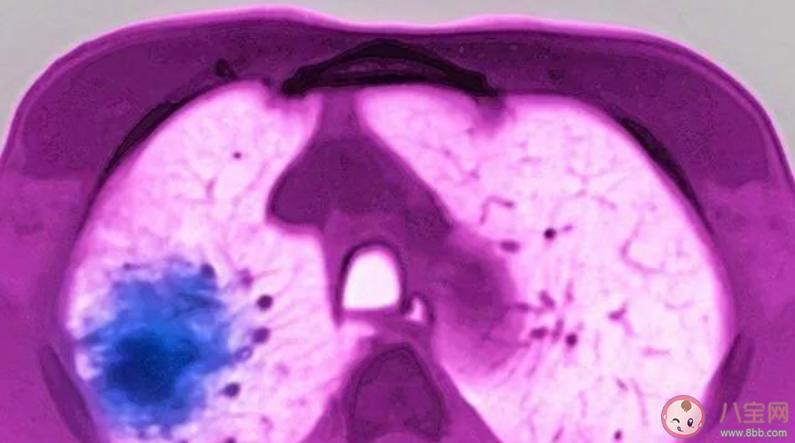

而如果患者是出現(xiàn)發(fā)熱、干咳、腹瀉、乏力的癥狀,且近期有高危接觸史,則考慮為新型肺炎的可能。如果新型冠狀病毒核酸檢測陽性,肺部CT有病毒性肺炎表現(xiàn),考慮診斷新型冠狀病毒性肺炎,需要住院隔離治療。